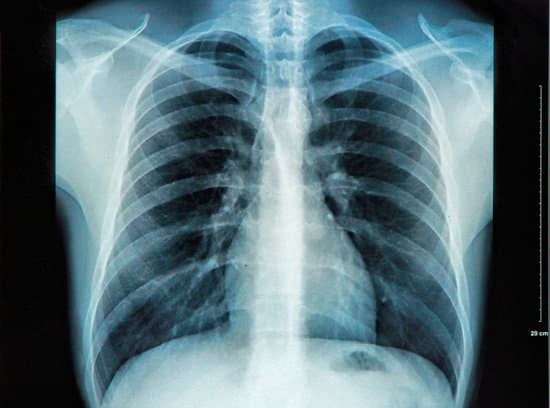

흉부 X선 촬영(Chest X-ray)은 가슴 부위를 X선으로 촬영하여 폐, 심장, 기도 등의 상태를 확인하는 의료 영상 검사입니다.

간단하고 빠르게 진행되는 검사로, 폐 질환, 심장 질환, 갈비뼈 이상 등을 진단하는 데 유용합니다.

폐와 기관지, 심장, 갈비뼈의 모양과 크기가 정상일 때는 특별한 소견이 없습니다.

폐렴, 폐결핵 등의 폐 질환이 있을 경우 폐에 흰색 음영이 나타납니다.

기흉의 경우, 폐가 수축되거나 폐 외부에 공기가 차는 소견이 보입니다.

심부전이나 심장비대의 경우, 심장의 크기가 비정상적으로 커져 있거나 흉막삼출이 보일 수 있습니다.

폐암의 경우, 폐에 혹이나 결절이 나타날 수 있습니다. 그러나 초기 폐암은 X선에서 확인되지 않을 수 있어 CT 스캔 등 추가 검사가 필요할 수 있습니다.

흉부 X선 촬영은 폐, 심장, 갈비뼈 등의 상태를 빠르게 확인할 수 있는 중요한 영상 검사입니다.

폐렴, 폐암, 기흉 등 다양한 폐 질환과 심장 상태를 진단하는 데 사용되며, 응급 상황에서도 유용하게 활용됩니다.